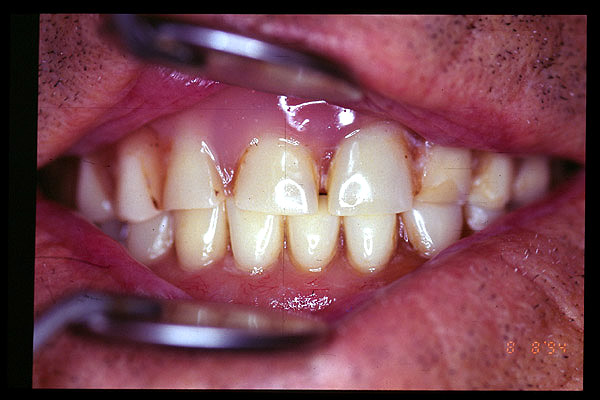

CM Desgaste por bruxismo, presencia de cálculo